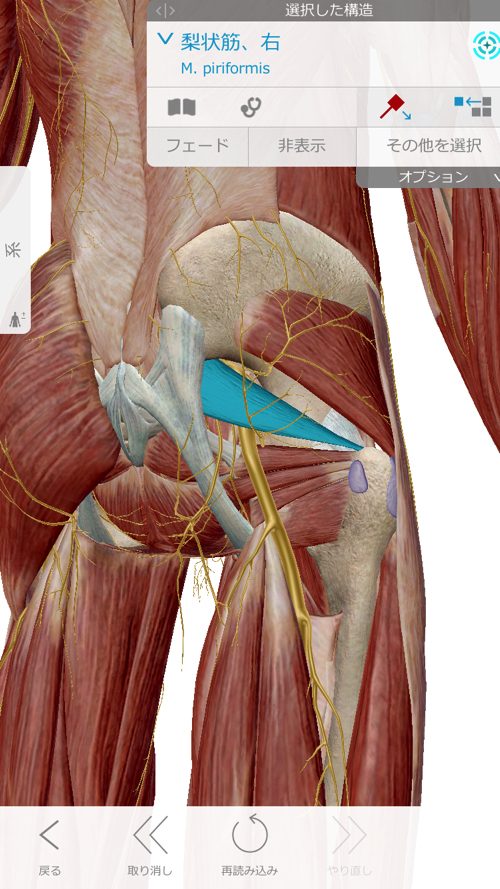

そしてここ梨状筋

これらの筋肉や腱の硬直を1つ1つ解いて

ズレやヨジレを丁寧に戻していく施術をさせて頂きました。